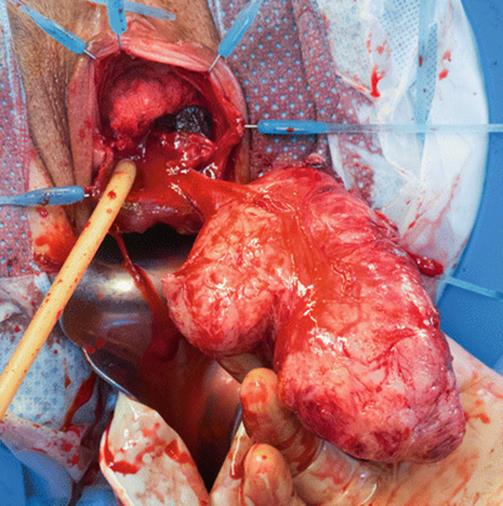

8.13 Large Urethral Leiomyoma Causing Urethral Obstruction

During her second pregnancy, the young patient in Figs. 8.43, 8.44, 8.45, 8.46, 8.47, 8.48, 8.49, 8.50, 8.51, 8.52, 8.53, 8.54, 8.55, 8.56, 8.57, and 8.58 presented with difficulty in voiding, tenderness in the anterior vaginal wall, and the feeling of a mass. Physical examination revealed a large, nontender, elastic, nonmobile mass inferior to the pubic bone. The mass displaced the urethra inferiorly.

The mass has been removed, and the remaining adhesions have been transected

Fig. 8.50

The distal and proximal urethras are wide open (like a cone with the tip representing the bladder neck). The bladder neck is the only area intact and competent. Construction of a neourethra will be performed

The specimen after removal. The final pathology showed a benign leiomyoma with areas of infarction and hyalinization